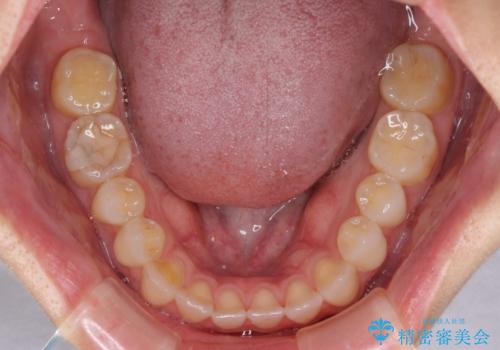

【モニター】狭い上顎歯列とオープンバイト 急速拡大装置を用いた矯正治療

- 前歯の開咬を気にして来院された患者様です。

上顎歯列が狭窄していたため、急速拡大装置により上顎骨を側方に拡大し、その後インビザラインにて矯正治療を行うこととしました。

舌の突出癖が開咬の原因であったので、改善のための舌トレーニングを行っていただきました。

舌トレーニングは後戻りにも大きく影響するため、とても重要なトレーニングです。